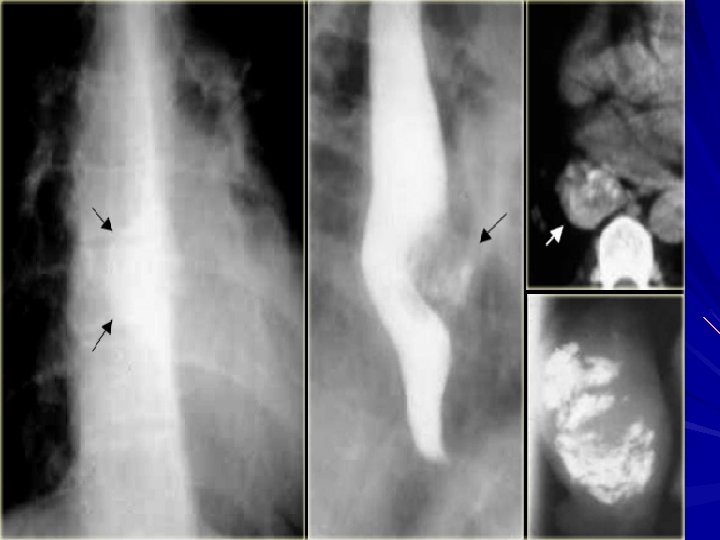

Diagnosis CXR may show air-fluid level Barium study quite dilated, and an airfluid level may be secondary to retained secretions. The classic finding is a gradual tapering at the end of the esophagus, similar to a bird's beak Upper endoscopy is the next diagnostic test in a patient with dysphagia or suspected achalasia

Diagnosis Esophageal manometry has the highest sensitivity for the diagnosis of achalasia : – aperistalsis of the distal esophageal body – incomplete or absent LES relaxation – hypertensive LES Manometric variants of achalasia exist – The best known is vigorous achalasia – defined by the presence of normal to high amplitude esophageal body contractions in the presence of a nonrelaxing LES

Diffuse Esophageal Spasm DES is a hypermotility disorder of the esophagus is seen most often in women and is often found in patients with multiple complaints The basic pathology is related to a motor abnormality of the esophageal body that is most notable in the lower two thirds of the esophagus

Diffuse Esophageal Spasm the esophageal contractions are repetitive, simultaneous, and of high amplitude

Symptoms and Diagnosis irritable bowel syndrome and pyloric spasm, may accompany DES, whereas other gastrointestinal problems, such as gallstones, peptic ulcer disease, and pancreatitis, all trigger DES The diagnosis of DES is made by an esophagram and manometric studies